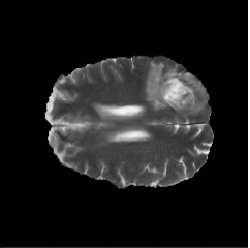

BraTS2018

This dataset comes from the Multimodal Brain Tumor Segmentation Challenge 2018 [4, 5, 35] and contains multi-parametric magnetic resonance imaging (mpMRI) scans of low-grade glioma (LGG) and high-grade glioma (HGG) patients. There are 210 HGG and 75 LGG cases in the training data, and each case has four types of MRI scans and three types of tumor subregion labels. In our experiments, we perform 2D segmentation on T2 images of the HGG cases to extract the whole tumor regions. The 2D slices with tumor areas smaller than 10 pixels are excluded for both GAN training and segmentation phases. In the GAN synthesis phase, all three labels are utilized to generate fake images. For segmentation, we focus on the whole tumor (regions with any of the three labels).

There are 210 HGG cases in the training data. Because we have no access to the test data of the BraTS2018 Challenge, we split the 210 cases into train (170 cases) and test (40 cases) sets. The train set is then sorted according to the tumor size and divided into 10 subsets equally, which are treated as data in 10 distributed medical entities. There are 11,057 images in the train set and 2,616 images in the test set. We conduct the following segmentation experiments: (1) Real-All. Training using real images from the whole train set (170 cases). (2) Real-Subset-n. Training using real images from the -th subset (medical entity), where . There are 10 different experiments in this category. (3) Syn-All. Training using synthetic images generated from a regular GAN. The GAN is trained directly using all real images from the 170 cases. (4) AsynDGAN. Training using synthetic images from our proposed AsynDGAN. The AsynDGAN is trained using images from the 10 subsets (medical entities) in a distributed fashion.

In all experiments, the test set remains the same for fair comparison. It should be noted that in the Syn-All and AsynDGAN experiments, the number of synthetic images are the same as that of real images in Real-All. The regular GAN has the same generator and discriminator structures as AsynDGAN, as well as the hyper-parameters. The only difference is that AsynDGAN has 10 different discriminators, and each of them is located in a medical entity and only has access to the real images in one subset.

(a) Input

(b) AsynDGAN

(c) Real

4.4.2 Results

The quantitative brain tumor segmentation results are shown in Table 2. The model trained using all real images (Real-All) is the ideal case that we can access all data. It is our baseline and achieves the best performance. Compared with the ideal baseline, the performance of models trained using data in each medical entity (Real-Subset-110) degrades a lot, because the information in each subset is limited and the number of training images is much smaller.

Our AsynDGAN can learn from the information of all data during training, although the generator doesn’t “see” the real images. And we can generate as many synthetic images as we want to train the segmentation model. Therefore, the model (AsynDGAN) outperforms all models using single subset. For reference, we also report the results using synthetic images from regular GAN (Syn-All), which is trained directly using all real images. The AsynDGAN has the same performance as the regular GAN, but has no privacy issue because it doesn’t collect real image data from medical entities. The examples of synthetic images from AysnDGAN are shown in Figure 5. Several qualitative segmentation results of each method are shown in Figure 4.